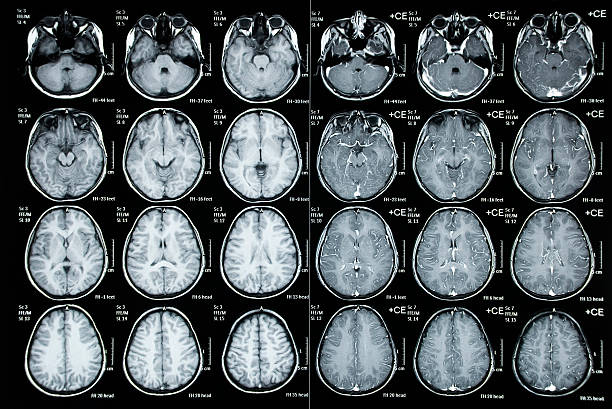

뇌동맥류는 뇌혈관벽이 약해지거나 손상되어 뇌혈관이 넓어지거나 부풀어 오르는 질환이다.. 뇌동맥류는 대개 무증상, 우연히도 발견. 그러나 뇌동맥류가 크거나 부위에 압통이 있는 경우, 이번에는 뇌동맥류 증상에 대해 자세히 알아보도록 하겠습니다..

뇌동맥류는 두통의 주요 원인 중 하나입니다.. 뇌동맥류로 인한 두통은 대개 갑자기 시작되며, 매우 심각하고 지속적인 통증을 일으킴. 두통의 위치는 뇌동맥류의 위치와 관련이 있을 수 있습니다..

뇌동맥류는 뇌로의 혈액 공급을 방해할 수 있습니다.. 그것으로 인한 현기증, 착란, 졸음, 폐색 등의 증상이 나타날 수 있습니다.. 이러한 증상은 일시적일 수 있지만, 뇌동맥류의 크기와 위치에 따라 지속적으로 발생할 수 있습니다..

뇌동맥류가 뇌의 시각 중심에 있을 때 시력 문제가 발생할 수 있습니다.. 시력이 저하되거나 시야가 제한될 수 있습니다.. 뇌동맥류가 크거나 압통이 있는 경우 이러한 증상이 더 두드러질 수 있습니다..

뇌동맥류가 언어나 인지 기능을 담당하는 뇌 부위에 있을 때, 말을 더듬거나 이해하기 어려울 수 있습니다.. 이러한 증상은 뇌 동맥류의 위치와 크기에 따라 심각도가 다를 수 있습니다..

크거나 부드러운 뇌동맥류는 뇌졸중으로 이어질 수 있습니다.. 뇌졸중은 뇌혈관에 혈전이 생기거나 출혈이 생겨 뇌의 기능이 일시적 또는 영구적으로 손상된 상태를 말한다.. 이러한 증상은 뇌동맥류의 위치와 크기에 따라 나타날 수 있습니다., 이는 응급 상황이며 즉각적인 치료가 필요합니다..

뇌동맥류가 뇌의 신경계에 위치하는 경우, 다양한 신경학적 증상이 나타날 수 있습니다.. 예를 들어, 뇌동맥류가 뇌신경을 압박하거나 손상시키는 경우, 마비는 얼굴이나 팔다리의 일부에 나타날 수 있습니다.. 또한, 뇌동맥류가 뇌의 일부 신경을 자극하거나 압박하는 경우, 불쾌한 감각이나 통증이 귀나 얼굴의 일부에 나타날 수 있습니다..

뇌동맥류는 뇌의 일부에 위치하거나 뇌의 일부로의 혈액 공급을 차단합니다., 발작을 일으킬 수 있습니다. 발작은 뇌의 신경 세포가 비정상적으로 활성화되어 기능이 일시적으로 손상되는 상태입니다.. 뇌동맥류는 발작을 일으킬 수 있습니다., 이러한 증상이 나타나면 정확한 원인을 파악하고 적절한 치료를 받아야 합니다..

뇌동맥류가 출혈을 일으키거나 뇌로의 혈액 공급을 심각하게 방해하는 경우, 혼수가 발생할 수 있습니다.. 이러한 증상은 응급 상황으로 간주되며, 즉각적인 치료가 필요합니다. 뇌동맥류는 다양한 증상을 유발할 수 있습니다., 이러한 증상이 나타나면 신속한 의학적 진단과 치료가 필요합니다.. 뇌동맥류의 크기와 위치에 따라 증상의 정도와 발생 가능성이 달라집니다., 증상이 나타나면 전문의와 상담 필요.